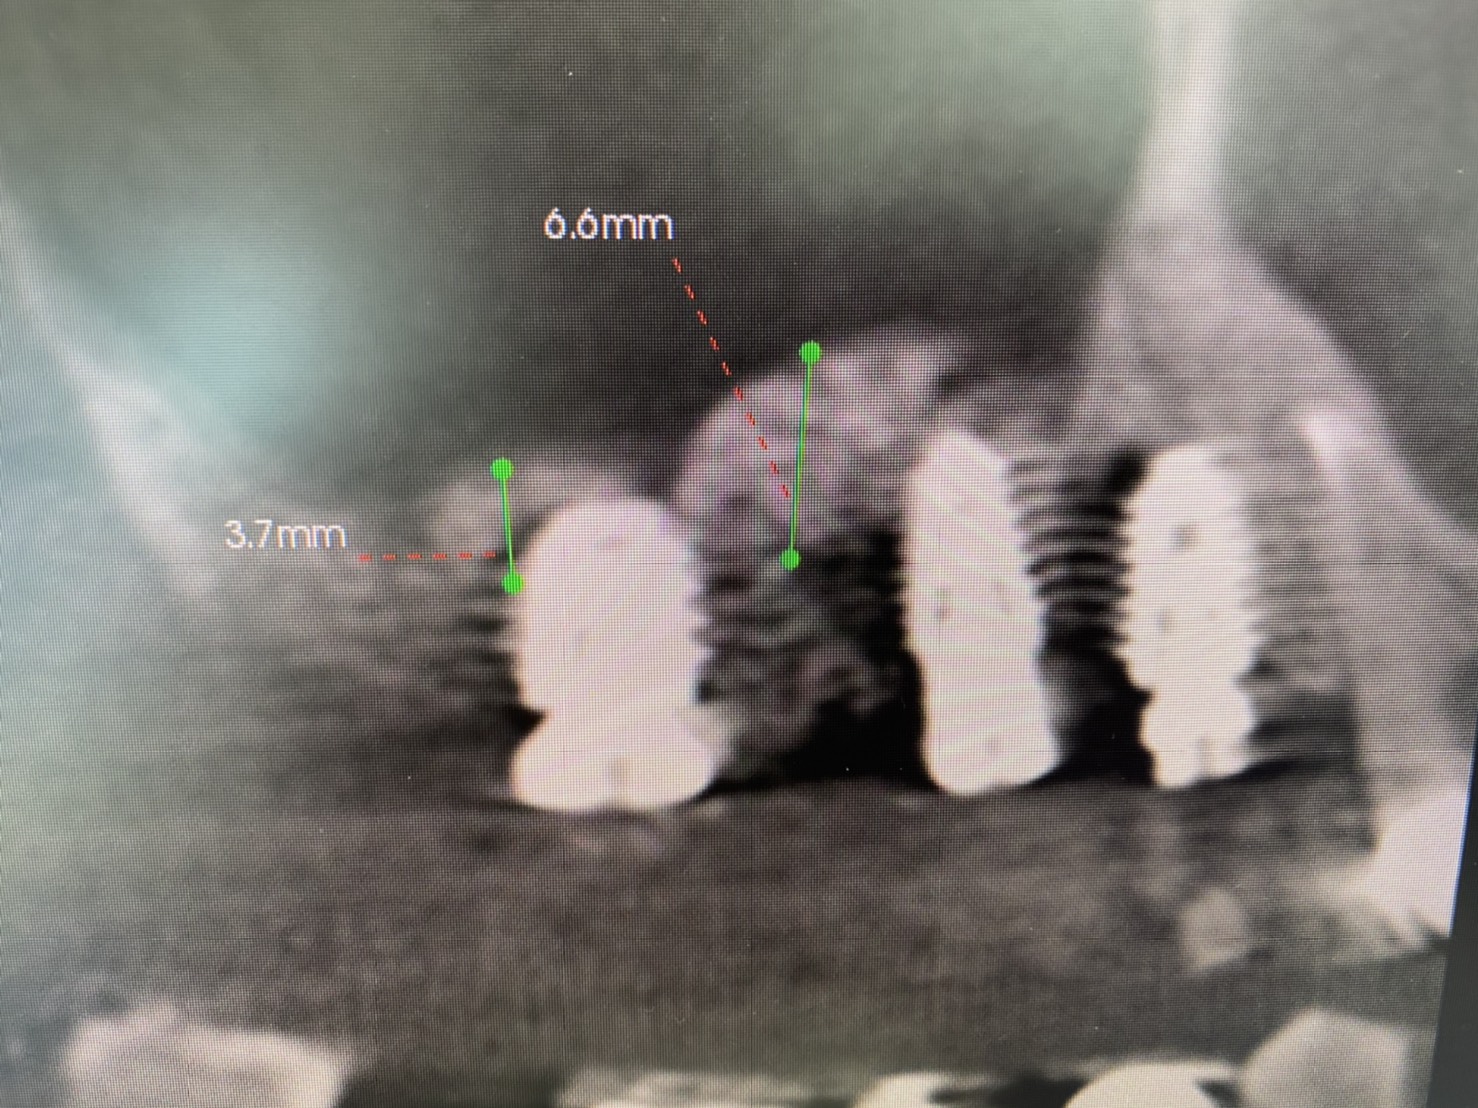

術前CT画像に示すよう、残存骨の高さは僅かしかないので、造骨の為にソケットリフトを併用しなければなりません。

更に5.6番の間には、膜を挙げ易くする為にベント、スリット等の工夫を設置、内圧減少の役割も考えます。

綺麗なドーム状にシュナイダー膜を持ち上げ造骨組織が収まっています。